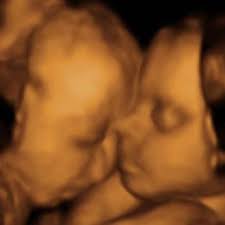

Baby connection roseville hours. The Baby Connection 4d 3d Hdlive Ultrasound Roseville. Im shocked it hasnt been reviewed before. You can feel confident in knowing that your ultrasound session will be provided by trained.

3101 likes 6 talking about this 5666 were here. A unique 3D4D fetal ultrasound company offering Hd Live now. Ladies if you are looking for an affordable 3d4d ultrasound The Baby Connection is the place to go. The Baby Connection allows you to see what your baby looks like before they are born by the use of our state-of-the-art 3D4D and HDlive fetal ultrasound. 267 reviews of The Baby Connection I cant believe that I had to add this business to Yelp. 20 avaliações detalhes de contato e horário de funcionamento para The Baby Connection em 1211 Pleasant Grove Blvd Ste 100 Roseville CA. I started looking for an ultrasound place once my hubby and I found out he would be leaving for 2 12 months to Basic Training for the Air Force. The Baby Connection Inc. 246 customer reviews of The Baby Connection.

The Baby Connection Roseville CA. If you are looking for baby connection roseville hours simply check out our links below. Gender determination upon request. I started looking for an ultrasound place once my hubby and I found out he would be leaving for 2 12 months to Basic Training for the Air Force. A unique 3D4D fetal ultrasound company offering Hd Live now. The Baby Connections is a unique keepsake fetal ultrasound company that provides a mobile service as well as office visitsOur mobile service is the only service of its kind in our areaWe are located in Roseville California and we service Sacramento Placer and Sutter countyWe make all this possible for you by bringing you the Voluson i which is a portable. The receptionists both times were super friendly and455251.